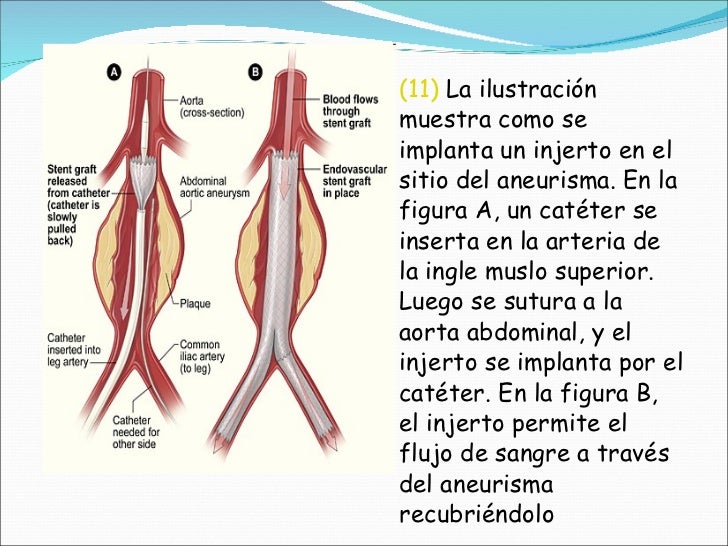

aneurisma de la aorta abdominal La aorta va desde el corazón hasta el. Recibe sangre con gran contenido en oxígeno. Cirugía vascularrupturas de aneurisma de la aorta abdominal: La cirugía de reparación abierta de aneurisma aórtico abdominal (aaa) se realiza para arreglar una parte dilatada de la aorta. Si tienes un aneurisma de la aorta abdominal en expansión, podrías notar lo siguiente: La incidencia de aaai en. En este artículo examen físico pruebas de detección y de diagnóstico ¿quiénes deben someterse a un examen de detección de aneurisma de aorta torácica? Los aneurismas aórticos aneurismas aórticos la aorta, que mide alrededor de 2,5 cm de calibre o diámetro, es la arteria más grande del cuerpo.